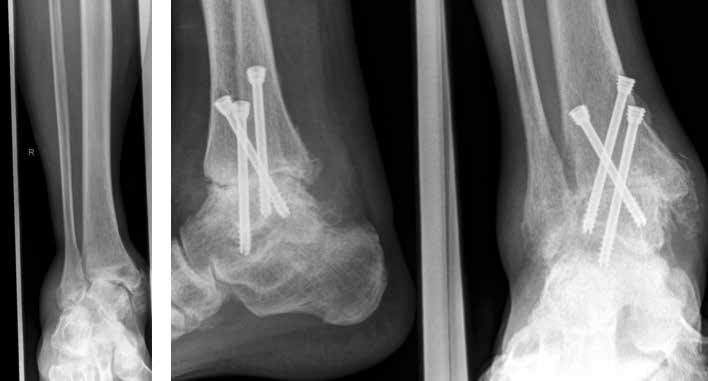

In ausgeprägten Fällen von Arthrose, oft mit Instabilität im oberen Sprunggelenk (Abb. 7), schwerwiegendem Funktionsverlust und starker Schmerzausprägung, ist nach wie vor die Arthrodese die Therapieoption der Wahl. Dadurch sollen die Achskongruenz wiederhergestellt und die Schmerzen eliminiert werden. Gleichzeitig bedeutet dieser Schritt jedoch, dass keine weitere operative Eskalation mehr möglich ist. Meist kommen die tibiotarsale oder tibiatalar-calcaneare Arthrodese zum Einsatz. Entscheidend für die Wahl des Arthrodeseverfahrens sind der Schweregrad der degenerativen Gelenkveränderungen, der Schmerz und die Stellungsverhältnisse im Subtalargelenk.

Eine Sonderform stellt die Talusnekrose dar, die ebenfalls zu schwerwiegenden Destruktionen und Achsfehlstellungen im OSG führt. Das Mittel der Wahl im fortgeschrittenen Stadium (Abb. 8a) ist hier die Arthrodese des OSG und des unteren Sprunggelenks (USG) mittels Arthrodesennagel (Abb. 8b).